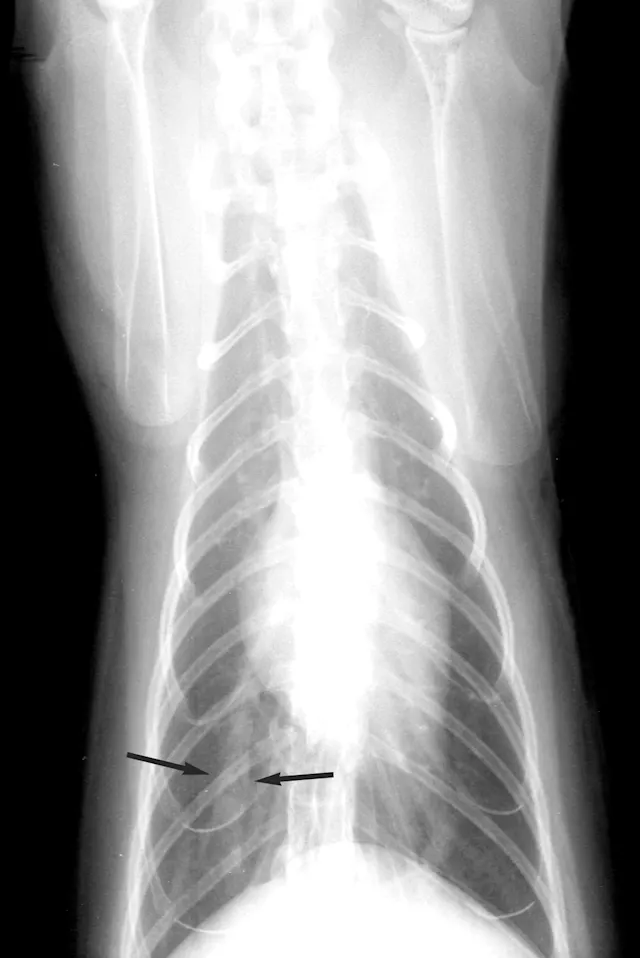

The cardiac silhouette of a cat with heartworms rarely has the "inverse D" appearance, or main pulmonary artery bulge, as seen in dogs. Cats more typically demonstrate radiographic findings compatible with feline bronchial disease ("asthma"). Nevertheless, certain findings, such as a caudal lobar pulmonary artery larger than 1.6 times the ninth rib at the ninth intercostal space, are quite suggestive of heartworm disease.